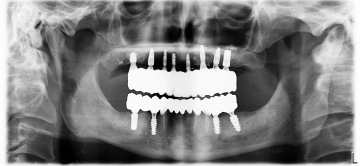

Každá implantologická léčba začíná pečlivým klinickým vyšetřením a 3D RTG (CBCT) diagnostikou.

Na základě získaných dat navrhujeme individuální léčebný plán, který vychází z anatomie, funkce a dlouhodobé stability budoucího řešení.

Výkony provádíme v lokální anestezii a za přísných hygienických a chirurgických standardů. K přesné diagnostice využíváme 3D RTG (CBCT), díky kterému můžeme naplánovat zákrok s maximální přesností.